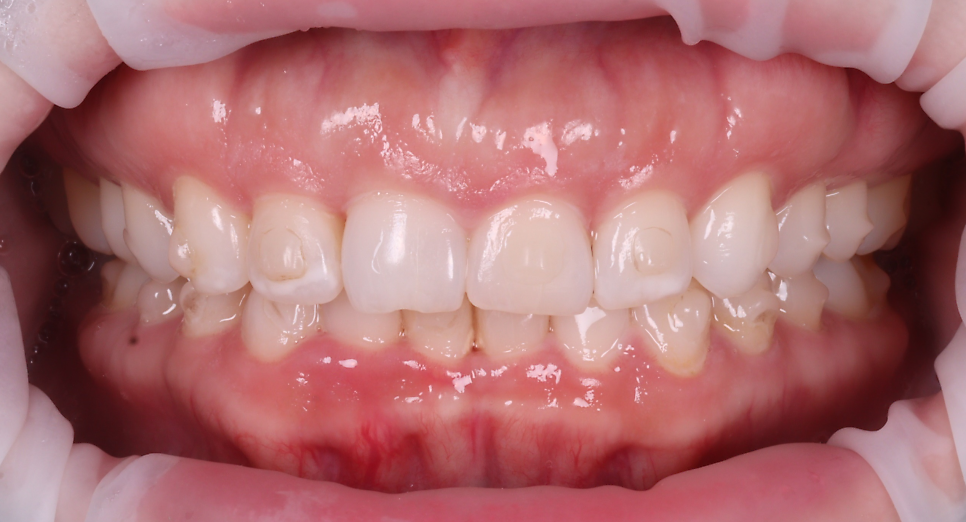

미국에서는 치아가 '크고 밝은 것'을

굉장히 선호하는데요.

환자분도 치아가 짧아 보여서

더 컸으면 좋겠다고 말씀해 주셨습니다.

아래 앞니는 전체적으로 교모(씹으면서 생긴

닳은 것)이 심했는데 일단 위 앞니를 먼저

해결하기를 원하셔서 지켜보기로 했습니다.